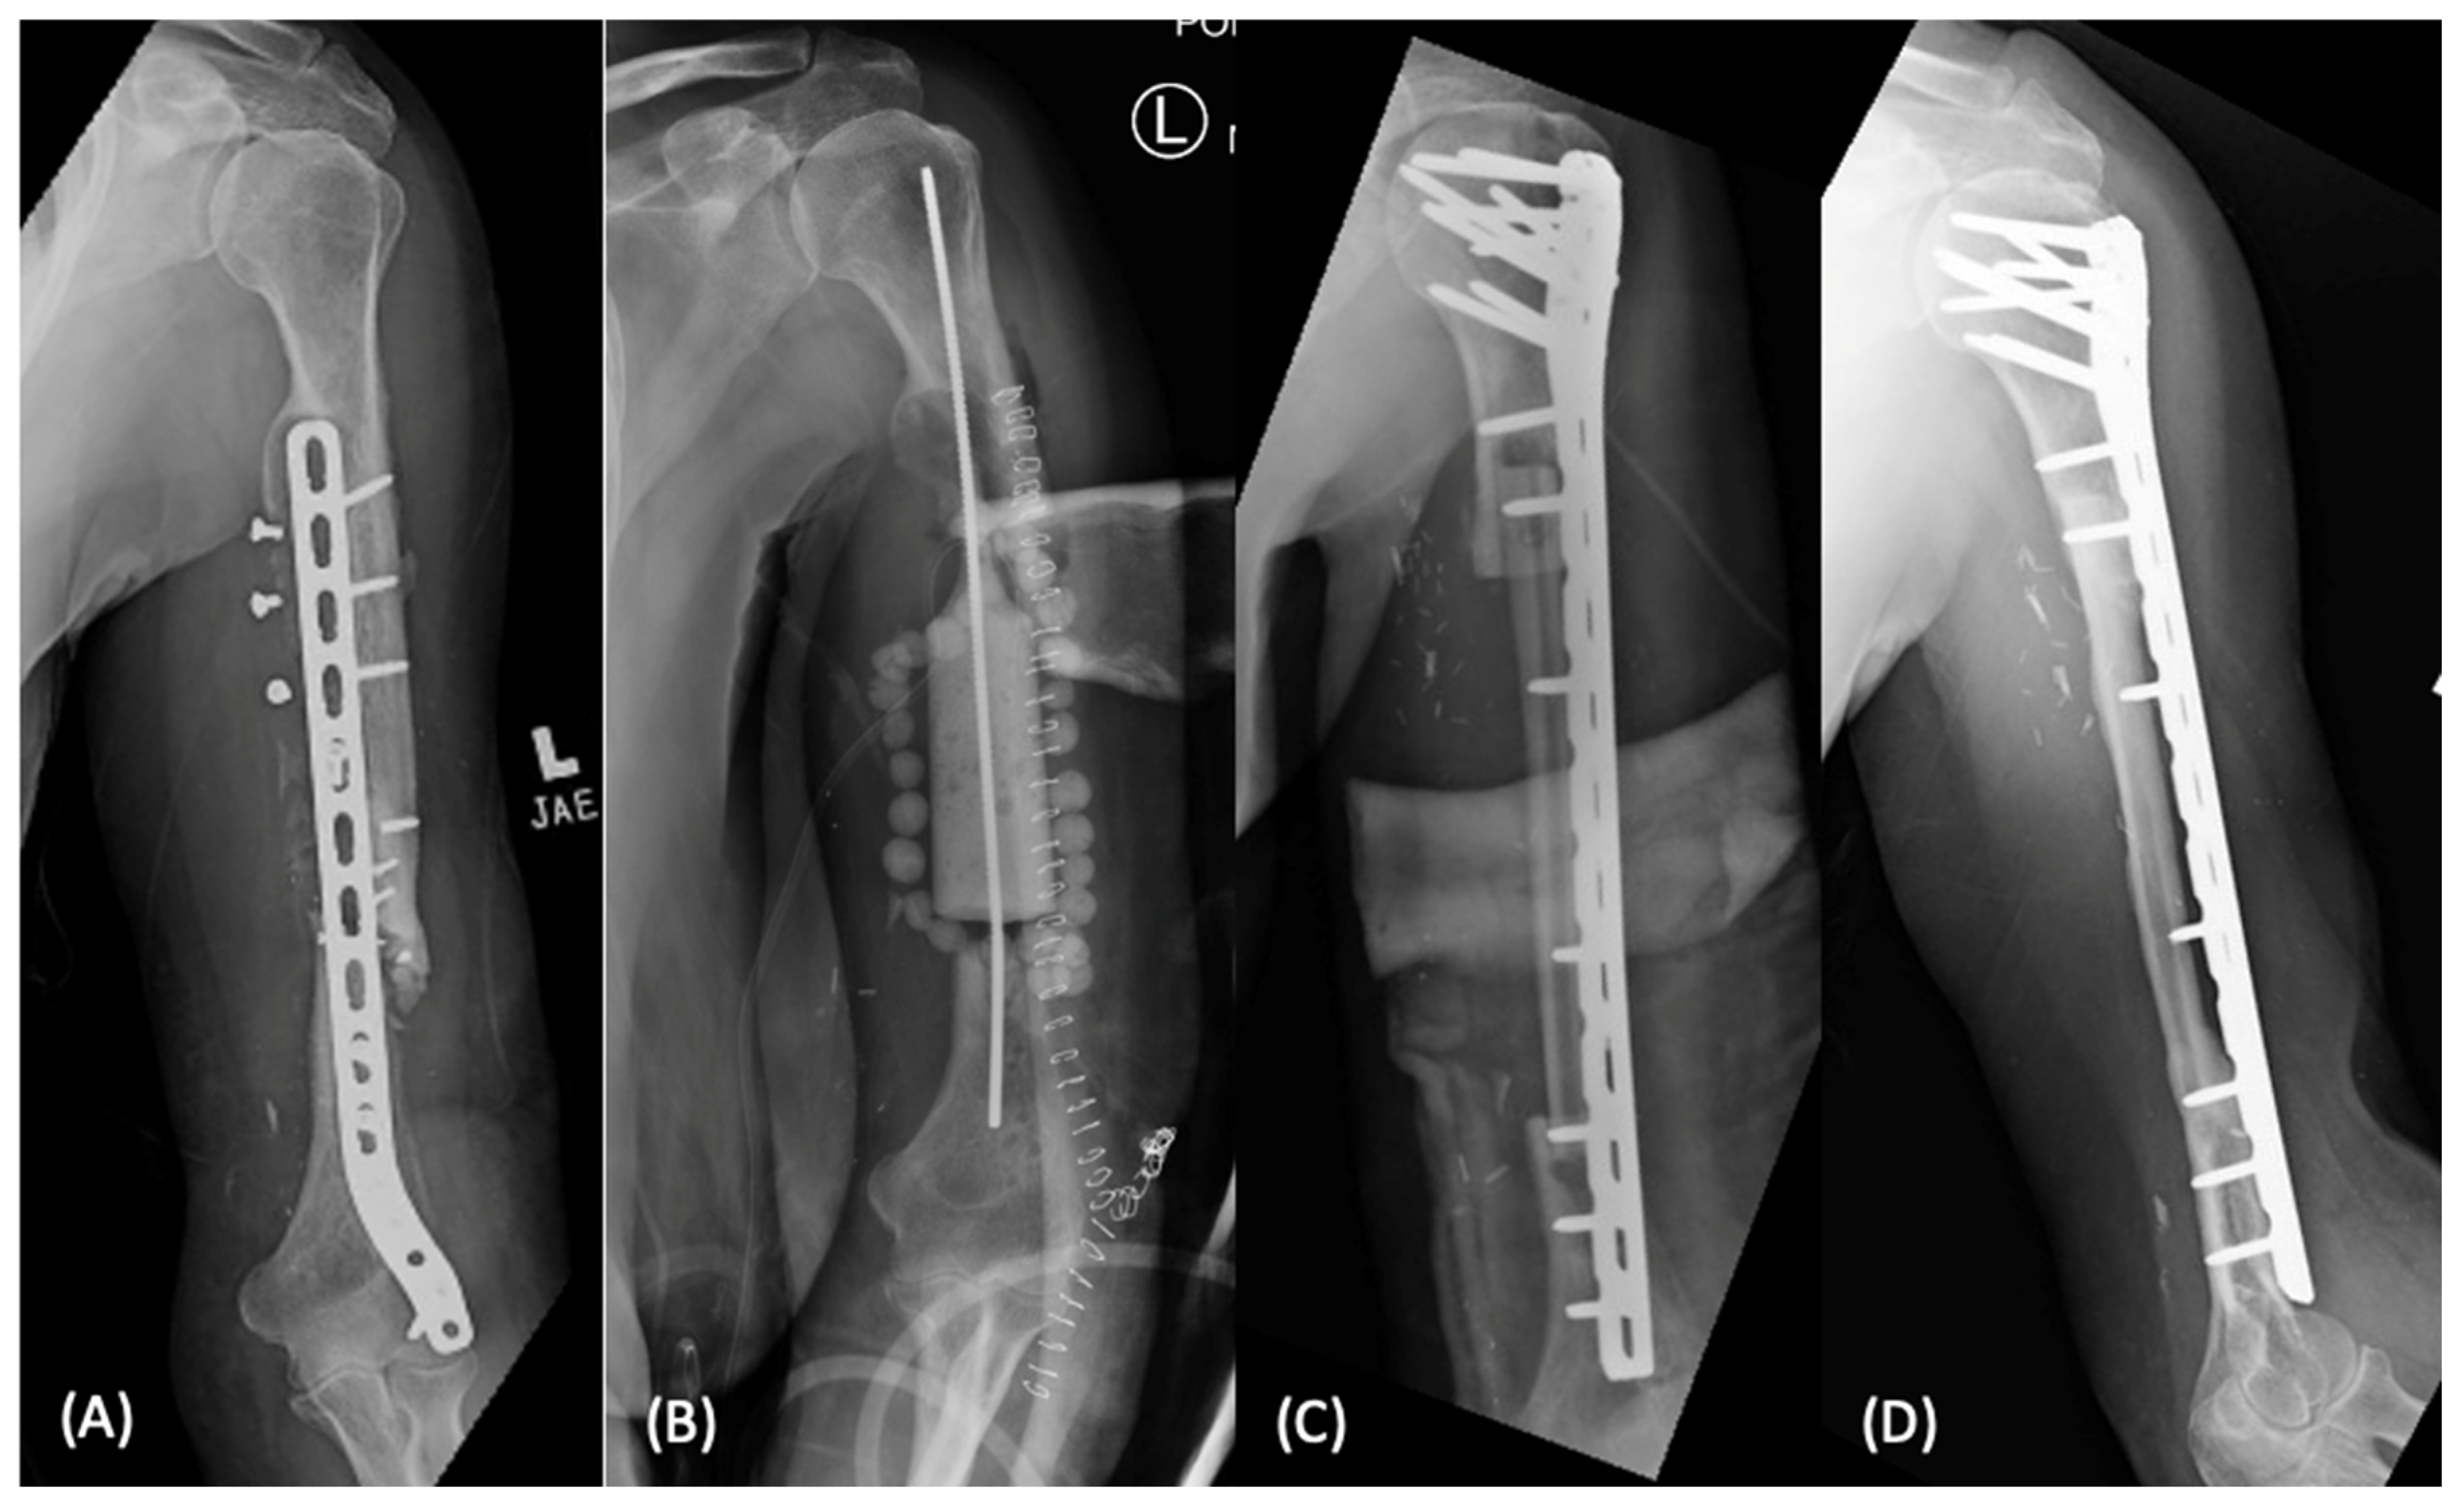

2.1.2. Distraction Osteogenesis

2.1.3. Vascularized Bone Grafting